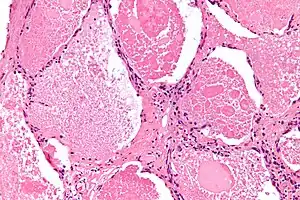

| Micrograph of pulmonary alveolar proteinosis, showing the characteristic airspace filling with focally dense globs referred to as chatter or dense bodies. H&E stain. | |

Lung washings or tissue for histopathologic analysis are most commonly obtained using bronchoalveolar lavage and/or lung biopsy.[12] Characteristic biopsy findings show filling of the alveoli (and sometimes terminal bronchioles) with an amorphous eosinophilic material, which stains strongly positive on PAS stain and the PAS diastase stain. The surrounding alveoli and pulmonary interstitium remain relatively normal.[13] Electron microscopy of the sample, although not typically performed due to impracticality, shows lamellated bodies representing surfactant.[14] An alternative diagnosis with similar histomorphologic findings is Pneumocystis jirovicii pneumonia.[14]

Lung washings characteristically yield a fluid which is "milky"composition. Under the microscope, samples show 20-50 micrometer PAS-positive globules on a background of finely granular or amorphous PAS-positive material. There is typically a low numbers of macrophages and inflammatory cells (although this is variable).[13][14]